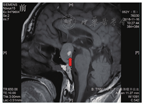

患者男,52岁,于2018年11月1日主诉"中上腹胀痛伴呕吐3 d"入院。入院前3 d无明显诱因出现中上腹胀痛,进食后明显,腹部胀痛时可见上腹部隆起,间断有恶心、呕吐,呕吐物为胃内容物,无隔夜宿食、凝血块和咖啡色物质,呈非喷射性,呕吐后中上腹胀痛可减轻,上腹部隆起可消退,食欲不振,偶感反酸、嗳气,体毛脱落明显,性欲减弱,无呕血、排黑便,无巩膜黄染、尿黄、皮肤黄,无头痛、头晕,无视物模糊,无肢体乏力,无乳腺胀痛、分泌乳汁等不适。拟"消化性溃疡并幽门梗阻?"收入院。体格检查:体温36.5 ℃,脉搏68次/min,呼吸频率20次/min,血压112/70 mmHg (1 mmHg=0.133 kPa),神情疲惫,体毛减少,双侧瞳孔等大、等圆,直径约为3 mm,对光反射灵敏,眼底和视力检查无明显异常。未见男性乳房发育。中上腹部饱满,中上腹轻度压痛,无反跳痛,可闻及振水音,肠鸣音为4~5次/min(正常参考值范围内)。四肢肌力、肌张力正常,病理征未引出。既往曾多次因胃溃疡、十二指肠溃疡发作入住福建医科大学附属三明市第一医院治疗。入院后多次查电解质:血钾波动于3.62~4.48 mmol/L,血钠波动于113.4~138.0 mmol/L,血氯波动于82.1~103.5 mmol/L。血浆渗透压为252.69 mOsm/L。血常规、肝肾功能、血糖、心肌酶、肌钙蛋白I、肌红蛋白、尿常规、血脂、凝血功能+D-二聚体+纤维蛋白降解产物、粪便常规+粪便隐血试验、游离三碘甲腺原氨酸(free triiodothyronine,FT3)、游离甲状腺素(free thyroxine,FT4)、促甲状腺激素(thyroid stimulating hormone,TSH)、CA125、CA19-9、癌胚抗原、甲胎蛋白、血淀粉酶均无异常。皮质醇无异常。血醛固酮0.05 μg/L(正常参考值为0.059~0.174 μg/L)。性激素6项:雌二醇17.0 ng/L(正常参考值为20~400 ng/L),孕酮0.02 μg/L(正常参考值为0.1~18.7 μg/L),促黄体生成素(luteinizing hormone,LH)、卵泡刺激素(follicle-stimulating hormone,FSH)、催乳素、睾酮均无异常。腹部立位片:腹部未见明显异常。心电图检查:窦性心律,窦性心动过缓,完全性右束支传导阻滞。彩色多普勒超声检查:胆囊结石,前列腺结石或钙化灶,肝脏、胰腺、脾脏、肾脏、膀胱、门静脉、肾血管、肾上腺区、腹部大血管声像图均未见明显异常,双侧输尿管未见明显扩张,胰腺和腹部主动脉周围未见明显肿大淋巴结。胃镜检查:胃窦息肉,胃窦溃疡(H2期),十二指肠球部溃疡(H2期),幽门圆形,开闭正常。全腹部CT检查:肝左叶小囊肿,胆囊结石,右肾小结石。头部和双肺CT检查:垂体占位,肿瘤伴出血?(图1)。胸部CT检查未见明显异常。头颅MRI检查:鞍区-鞍上占位,考虑垂体大腺瘤合并出血(大小约为2.7 cm×1.8 cm)(图2、图3)。入院后予艾司奥美拉唑抑酸,氯化钠补钠,营养支持治疗,并行胃肠减压,引流出墨绿色液体,每天量为600~1 100 mL。经上述治疗患者血钠恢复正常,无腹部胀痛、呕吐,生命体征平稳,转神经外科手术治疗,术后CT检查示无出血(图4),术后病理结果示垂体腺瘤(图5)。